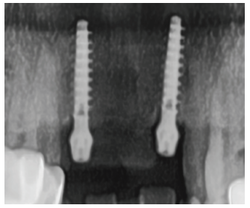

식립 1개월 후 연조직의 양호한 치유 상태와 순측의 풍부한 연조직 sealing을 관찰할 수 있다. 치조제와 치은연의 보존 및 개선도 관찰된다 [그림 10].

식립 2개월 후 zirconia 최종 보철물을 제작해 장착했고 순측의 연조직 형태가 수직적인 재생이 돼 발치 이전보다 개선된 모습을 볼 수 있다. thick gingival biotype으로 개선되면서 연조 직의 형태가 지금보다 더 풍융하게 개선될 것으로 예상된다 [그림 11, 12].